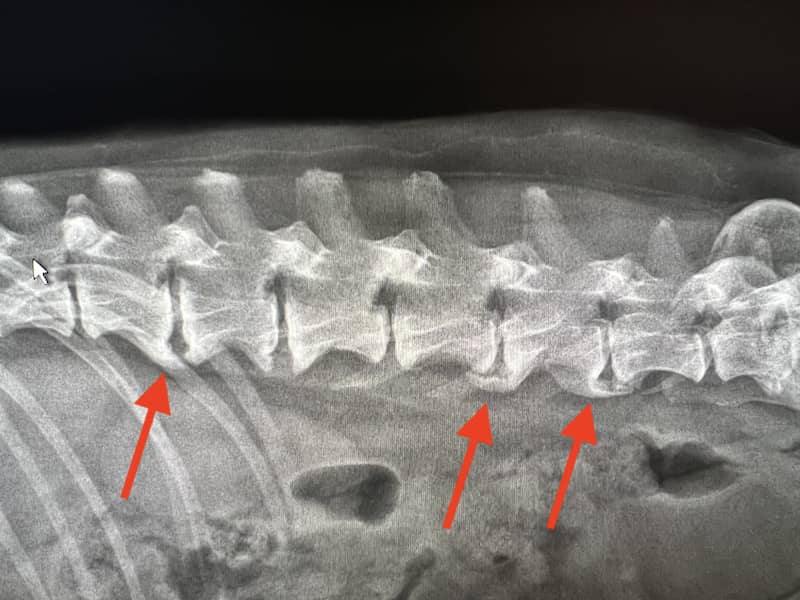

With dogs, fat pads typically start developing over your dog’s lower back or lumbar area (the top of their back legs). Sometimes, dog muscle wasting will show a more prominent spine, and the dog may develop a swayback (when they seem to sway back and forth more than usual while walking). This could mean nothing and simply indicate that your pup is just old, but it could also be a condition like spondylosis.

Normal dog spine versus one with spondylosis. Source

To know for sure, your vet will do a physical examination and perhaps take x-rays to determine whether your dog has the condition or not.